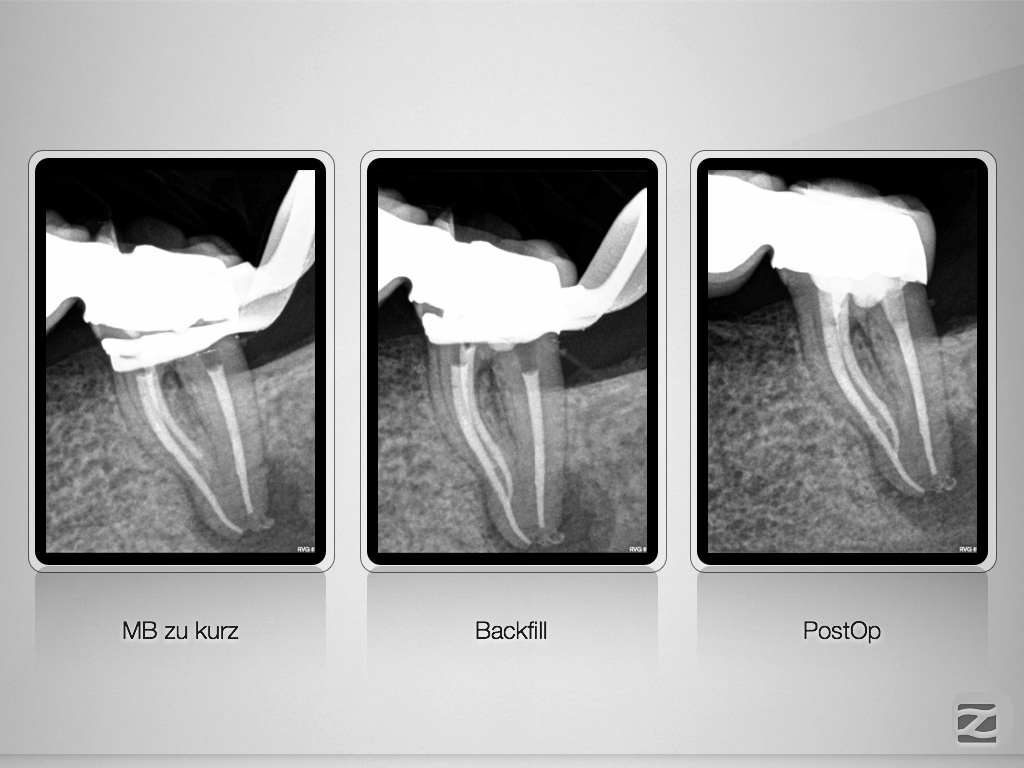

37D.008

Hyflex Fallbeispiel (2/3)